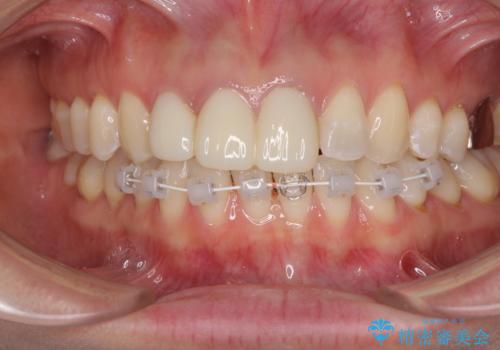

補綴治療に先立ち、下顎前歯の部分矯正を行い、前歯の咬み合わせの安定性向上を図りました。

当初は上顎の補綴治療のみを希望されていましたが、仮歯装着期間に上下の前歯の接触が気になったため、部分矯正を行うこととしました。